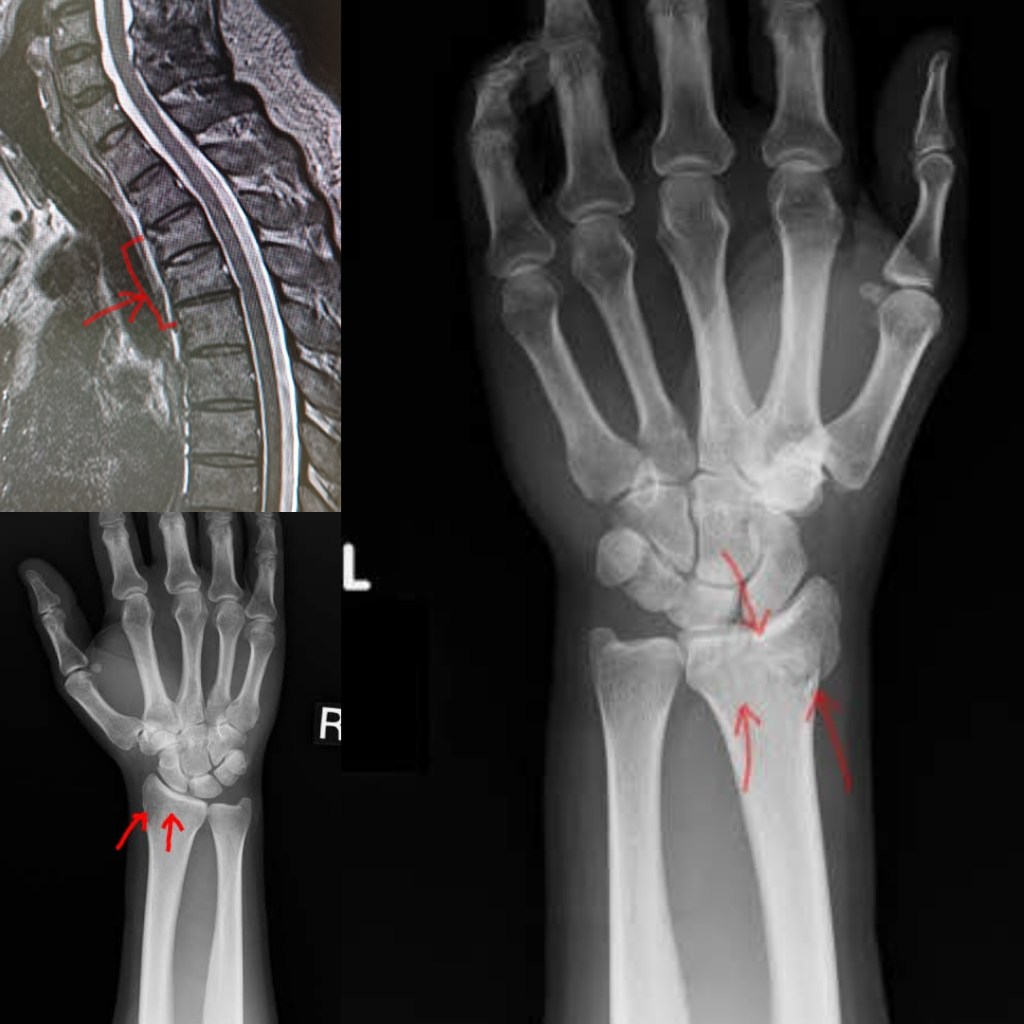

Later, at the hospital after some xrays and CT scans, the injuries were clear.

Rehab lasted a while. The back is still not right, the left wrist isn’t either but I’m no spring chicken and that wasn’t my first rodeo. I can still ride!